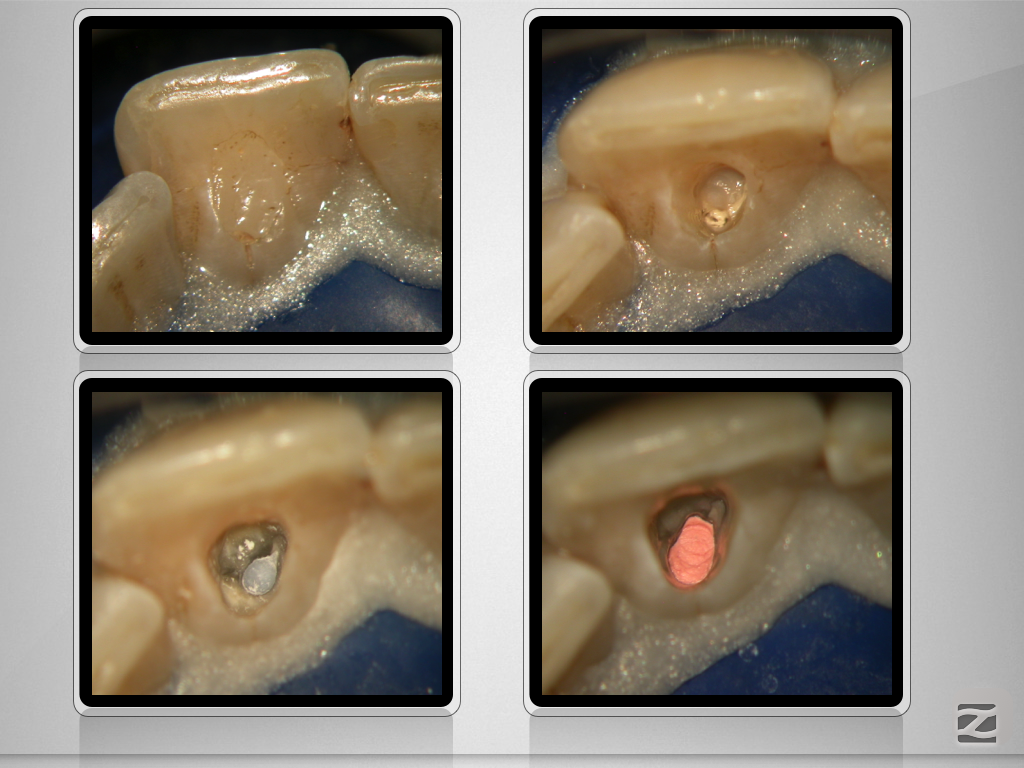

21D.006 Veröffentlicht 21. April 2017 am 1024 × 768 in Perforierende Resorption als Trauma(spät)folge